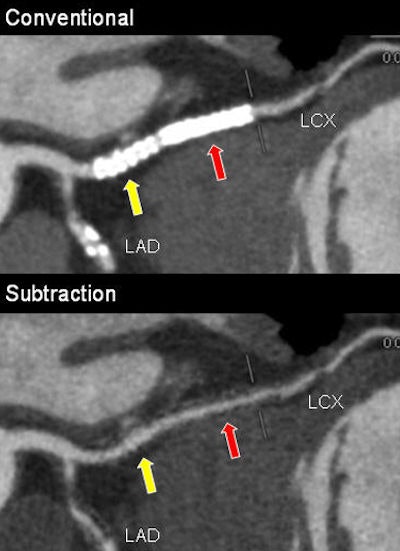

Digital subtraction CT angiography, like the conventional digital subtraction angiography (DSA) it is steadily replacing, works by subtracting precontrast from postcontrast-enhanced images to visualize anatomy in challenging environments where bone, soft tissue, or, in this case, metallic stents can create image artifacts.

Fifty-six stents couldn't be assessed before subtraction, compared with four after subtraction. Among the factors causing stent nonassessability, size was by far the most important, with smaller stents harder to assess.

Still, with the use of DSCTA, stent assessability improved from approximately 78% to 92% for 3.5-mm stents (p = 0.0503), from 61% to 90% for 3.0-mm stents (p = 0.0001), and from 37% to 81% for 2.5-mm stents (p = 0.0001).

"For the larger stents, there was no statistically significant difference" in assessability with or without DSCTA, Amanuma said. However, for 2.5-mm stents, the improvement in assessability was more than 40 percentage points.

"DSCTA improved visualization of the stent lumen, resulting in improved diagnostic capabilities in the evaluation of in-stent restenosis, especially in terms of specificity, which is very important," he said. "The frequency of restenosis is very small, so high specificity is important."